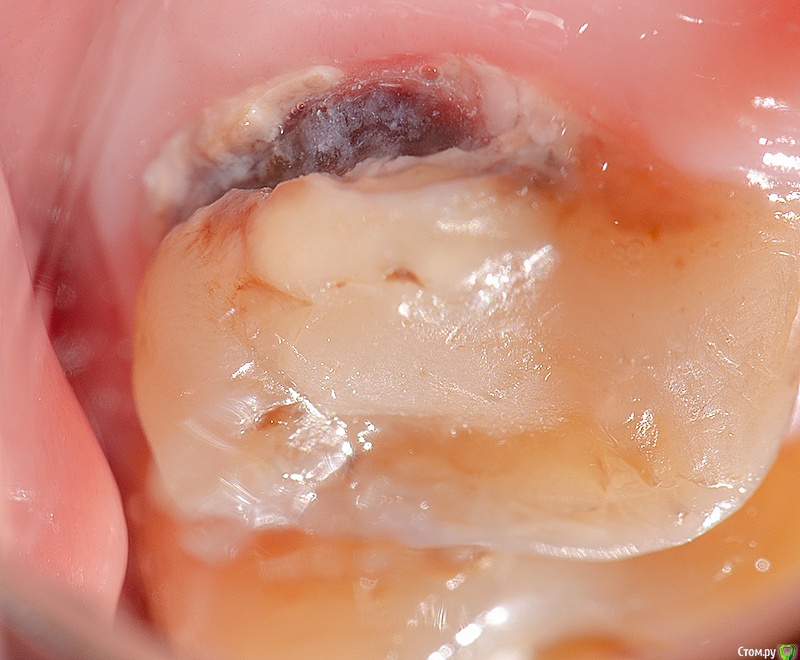

Kolchanov Опубликовано 15 февраля, 2019 Поделиться Опубликовано 15 февраля, 2019 Ну вот аналогичная ситуация Когда такое приходит, то на снисхождение нефиг и рассчитывать. Рублю с плеча все, что мешает. 2 Ссылка на комментарий

Romanson Опубликовано 21 февраля, 2019 Автор Поделиться Опубликовано 21 февраля, 2019 2.7 и 2.62.6 живойДесна в таком состоянии не после полировки, а десна в таком состоянии после того, как убрал все пораженные ткани, перед изоляцией.http://i.piccy.info/i9/e0b830f72e30b032457f7cf13917334e/1550767579/96207/1294807/1.jpghttp://i.piccy.info/i9/ffd5637596702fde9cd7407755e9c9eb/1550767594/68188/1294807/2.jpghttp://i.piccy.info/i9/39435906d80f5321e693a2d787031b97/1550767603/49844/1294807/3.jpg Что с такими зубами делать? Меня не учили. 1 Ссылка на комментарий

Бардо Опубликовано 21 февраля, 2019 Поделиться Опубликовано 21 февраля, 2019 Что с такими зубами делать? Меня не учили. Так все правильно сделали же. Чистенько и аккуратно. Мне правда после таких пломб хочется почему-то профессию сменить. Смотришь видео на фейсбуке - там все в микроскопах лечат фиссурный кариес или на контактах 1,5 мм от сосочка у пациентов с идеальной гигеной - сплошное благорастворение. Потом приходишь на работу и давай десну резать и матрицу туда загонять с клином ) 7 Ссылка на комментарий